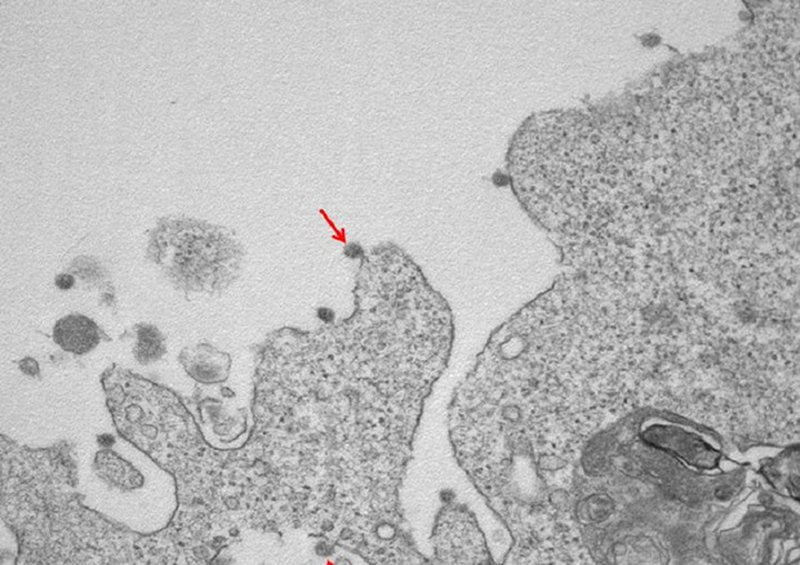

Tashmë “korona” ka një “fytyrë”. Kanë dalë imazhet e para bardhezi të virusit SarsCoV2 i izoluar në Lombardi në spitalin “Sacco” në Milano. Imazhet e mikrografisë elektronike tregojnë grimcat virale të bashkangjitura në membranat qelizore dhe kurorën e tyre tipike të glikoproteinave sipërfaqësore.

Në një zmadhim prej 30000X, vërehen grimcat virale të SarsCov2 (të treguar nga shigjeta), të bashkangjitura në membranat në sipërfaqe dhe qelizat e brendshme, të përdorura për izolim.